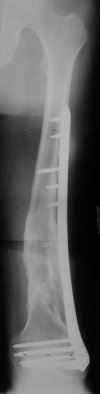

Synthes 4.5 mm LCP (Locking Condylar Plate) is slightly different, more anatomical shape and larger (wider) than original LISS. I personally use it when I have more difficult, Type C fractures where larger incision is necessary in order to reconstruct the joint.

For cases with less comminution and those that require longer plates (more involvement of distal third of femur), I rather go with LISS because is

possible to put the screws truly percutaneously (stab incisions, outside guide). Both systems are available and in use... :) .

Dr. Melamed: Principles for LISS and LCP are the same, again - LISS has outrigger helping for more percutaneous technique.